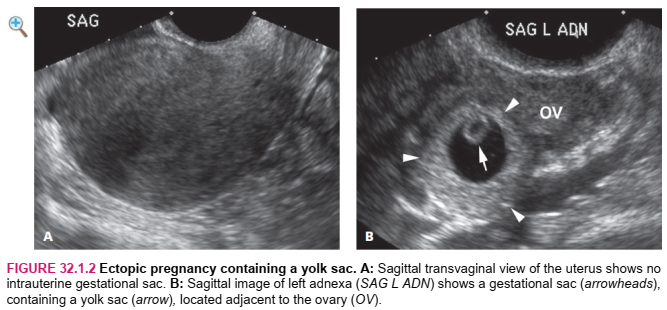

The sonographic finding that is definitive for ectopic pregnancy is visualization of a fluid-filled sac that lies outside the uterine cavity and contains either an embryo with cardiac activity (Figure 32.1.1) or a yolk sac (Figure 32.1.2). A more common, although less definitive, ultrasound finding in a woman with ectopic pregnancy is a complex extraovarian adnexal mass. In some cases, the mass is a fluid collection surrounded by a thick echogenic outer rim, termed a “tubal ring” (Figure 32.1.3), whereas in other cases, the mass has a solid or mixed solid and cystic appearance (Figure 32.1.4). There is sometimes a large amount of free intraperitoneal fluid and/or clotted blood in the pelvis (Figure 32.1.5).

Phát hiện siêu âm xác định mang thai ngoài tử cung là hình dung một túi chứa đầy chất lỏng nằm bên ngoài khoang tử cung và chứa một phôi thai có hoạt động tim (Hình 32.1.1) hoặc một túi noãn hoàng (Hình 32.1.2). Một phát hiện siêu âm phổ biến hơn, mặc dù ít chắc chắn hơn ở một phụ nữ mang thai ngoài tử cung là một khối phụ phức tạp ngoài buồng trứng. Trong một số trường hợp, khối này là một tập hợp chất lỏng được bao quanh bởi một vành ngoài dày có phản âm, được gọi là “vòng ống dẫn trứng” (Hình 32.1.3), trong khi trong các trường hợp khác, khối có dạng rắn hoặc hỗn hợp rắn và dạng nang (Hình 32.1 .4). Đôi khi có một lượng lớn dịch màng bụng tự do và / hoặc máu đông trong khung chậu (Hình 32.1.5).

HÌNH 32.1.2 Thai ngoài tử cung chứa một túi noãn hoàng. A: Hình ảnh trên siêu âm ngả âm đạo mặt cắt Sagittal của tử cung cho thấy không có túi thai trong tử cung. B: Hình ảnh mặt cắt Sagittal của phần phụ bên trái (SAG L ADN) cho thấy một túi thai (đầu mũi tên), chứa một túi noãn hoàng (mũi tên), nằm cạnh buồng trứng (OV)